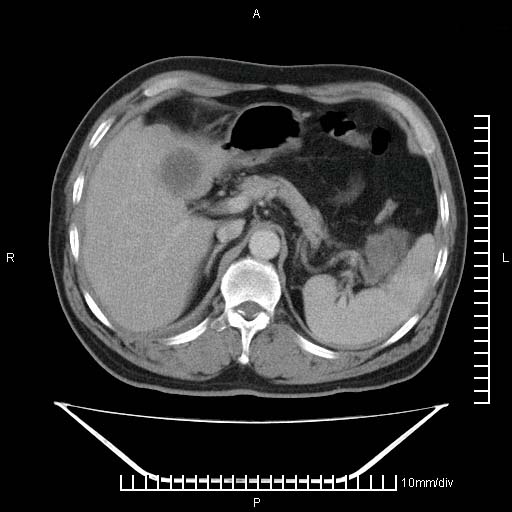

标题: CT25082:肝脏增强:男性,70岁 [打印本页]

标题: CT25082:肝脏增强:男性,70岁

患者以心脏疾病收住院,腹部无明显症状,b超查肝脏有占位。

增强效果不理想。考虑转移,胆囊壁明显增厚,不排除胆囊癌肝转移。

病灶无强化,考虑囊肿。

牛眼征,中心坏死无强化,外缘强化,最外缘又见低密度,考虑转移,与脓肿鉴别

肝内多发转移瘤,右下肺炎症并少量胸水。胃壁增厚建议胃镜,胰尾部“病变”为肠管。

1)肝脏多发性转移瘤(不排除胰尾癌转移所致可能)。2)腹水。3)右侧少量胸腔积液。

ct25082 结果:转移瘤

外院mr结果:胰尾恶性占位。